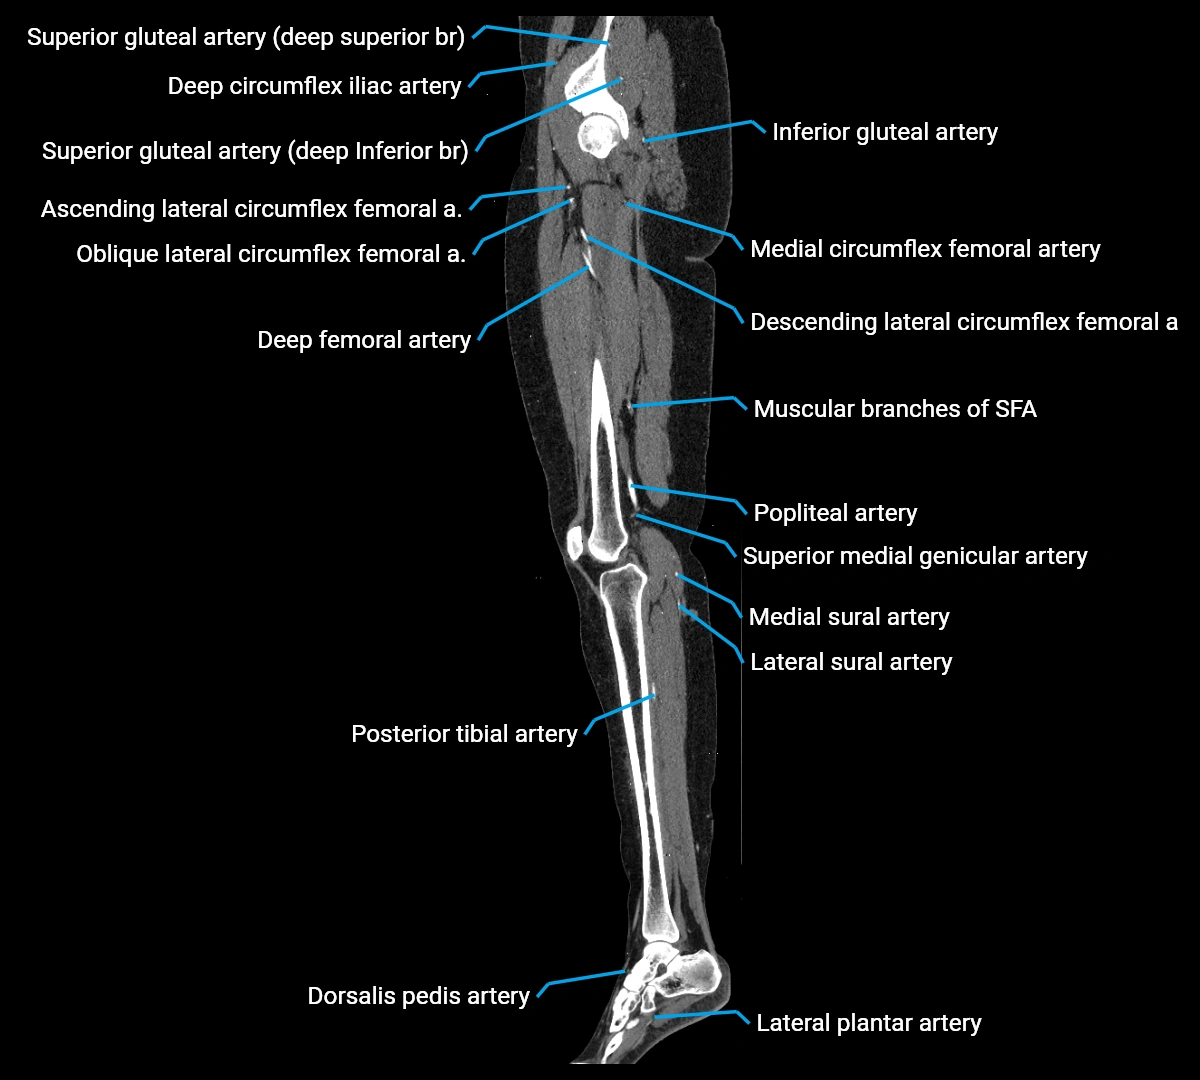

CT Appearance

Non-contrast CT:

• Appears as a tubular soft tissue structure anterior to vertebral bodies

• Calcified atherosclerotic plaques appear as hyperdense foci along the wall

• Useful for screening abdominal aortic aneurysm (AAA) size and mural calcification

Contrast-enhanced CT (CTA):

• Gold standard for abdominal aortic imaging

• Provides excellent detail of lumen, wall, aneurysm, thrombus, and branch vessels

• Multiplanar and 3D reconstructions help in aneurysm measurement, stent graft planning, and dissection evaluation

• Detects acute rupture, traumatic injury, or occlusion with high sensitivity

CT images

image